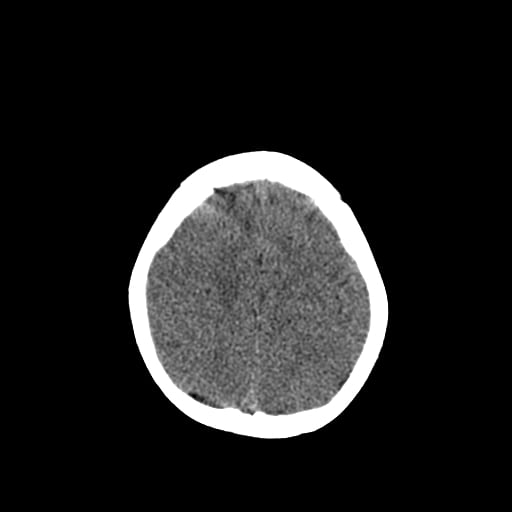

Age: 1

Sex: Male

Indication: Fall